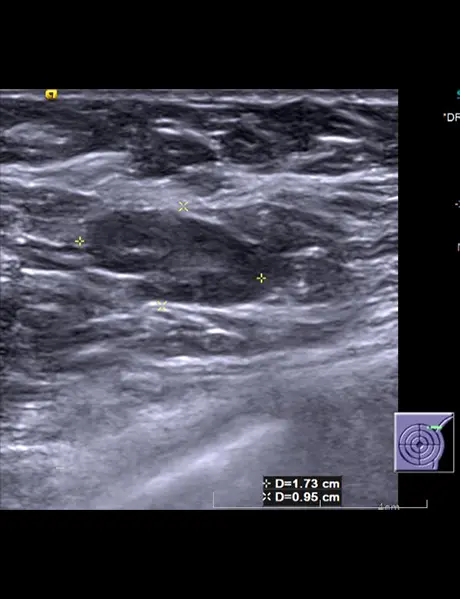

A) & B) Large area of abnormality in upper half of left breast with dominant central mass (straight white arrow). Multiple dilated and thickened ducts (straight red arrow)are seen extending from the mass.

C) Multiple lymph nodes (curved white arrow) with thickened cortices in left axilla

• In USG, breast tuberculosis can be seen as

• Nodular - Indistinct heterogenous hypoechoic mass

• Diffuse - form Ill defined hypoechoic masses.

• Skin thickening and duct ectasia are the other findings that are seen.

• Ipsilateral axillary adenopathy is present in 20 69% of cases.